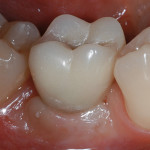

Corone singole su impianti a connessione conometrica nei settori posteriori dei mascellari: carico dilazionato...

Riassunto

Questo studio prospettico, controllato e randomizzato intende valutare sopravvivenza e successo di 270 impianti a connessione conometrica, a sostegno di corone singole, inseriti nei...